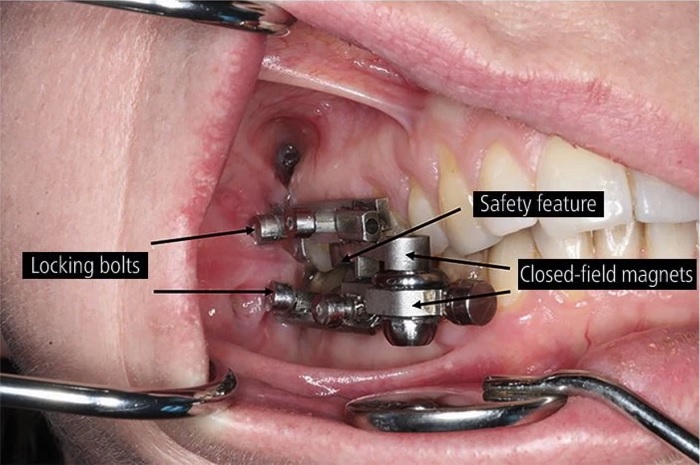

紐西蘭奧塔哥大學 (University of Otago) 的一支研究團隊和科學家共同研發出一款齒科飲食控制裝置 (The DentalSlim Diet Control),目前已裝在7位過重的女性身上進行實驗。這個裝置固定在上下排牙齒的後牙區,利用磁吸式的方式將嘴巴鎖上,張嘴時最大只能張開2毫米,能避免人們吃下過多固體的食物,強迫性的只能食用液態食物,進而達到節食減重的效果。

圖片來源 / BDJ

幫助研發裝置的保羅 (Paul Brunton) 教授表示,這個裝置沒有侵入性,佩戴的人能正常呼吸和講話,它主要是強迫佩戴者食用流質食物以達到有效的减肥效果。